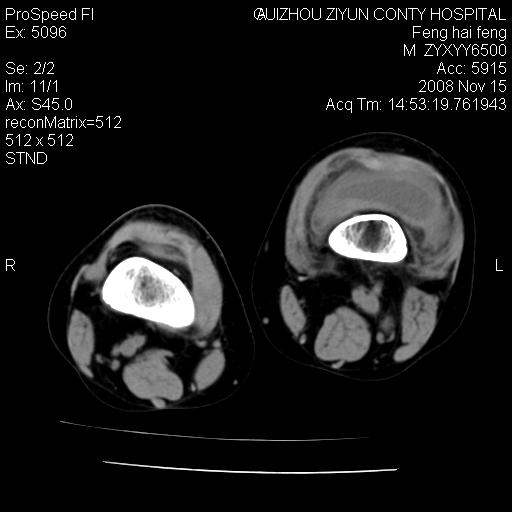

标题: CT16656:M 14Y 左膝关节肿胀一年余。其余病史不详。 [打印本页]

标题: CT16656:M 14Y 左膝关节肿胀一年余。其余病史不详。

考虑左侧髌骨结核;左膝关节滑膜肿胀、增厚,关节囊积液。

左膝滑膜型关节结核可能性大!支持!滑膜型关节结核主要ct表现:关节囊肿胀,积液,关节面见小破坏灶,并见点状死骨!

好大的左腿!考虑左侧髌骨结核,左膝关节滑膜肿胀、增厚,关节囊积液。

左侧髌骨结核;左膝关节滑膜肿胀、增厚,关节囊积液